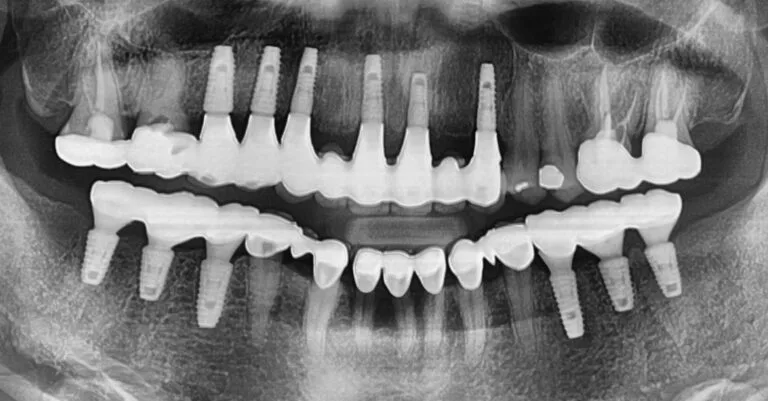

To thoroughly understand her bone structure, we began with a CBCT (Cone Beam Computed Tomography) scan, a sophisticated 3D X-ray providing a detailed blueprint of her jaw. Following a comprehensive consultation and the development of a tailored treatment plan, we decided on the placement of 12 dental implants. For optimal aesthetics in the upper front, we planned for tooth-colored abutments, while utilizing titanium abutments on the molars for enhanced durability. (You can learn more about these components in our blog post, ‘Custom Abutments of Dental Implants‘.) While our initial aim was to replace each missing molar with an implant, we strategically chose to forgo implants in two specific non-stress-bearing areas of the upper front, which also offered a more affordable option for the patient.

To ensure the highest precision and success, we utilized a surgical guide during the implant placement.

Surgical guides are invaluable in complex multiple implant cases. By allowing for meticulous pre-operative planning and virtual surgical simulations, we can optimize the implant placement strategy and develop the most effective treatment plan. Utilizing a surgical guide enabled us to successfully place all 12 implants in a single, efficient session. (For more information on surgical guides, please refer to my blog post about the ‘Surgical Guide for Dental Implant’.)